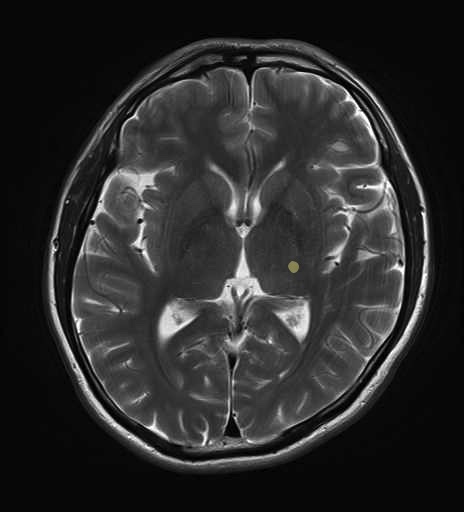

運動系 錐体路系に色を付けました。

■皮質脊髄路(いわゆる錐体路):一次運動野から脊髄遠隔の下位運動ニューロン細胞体まで